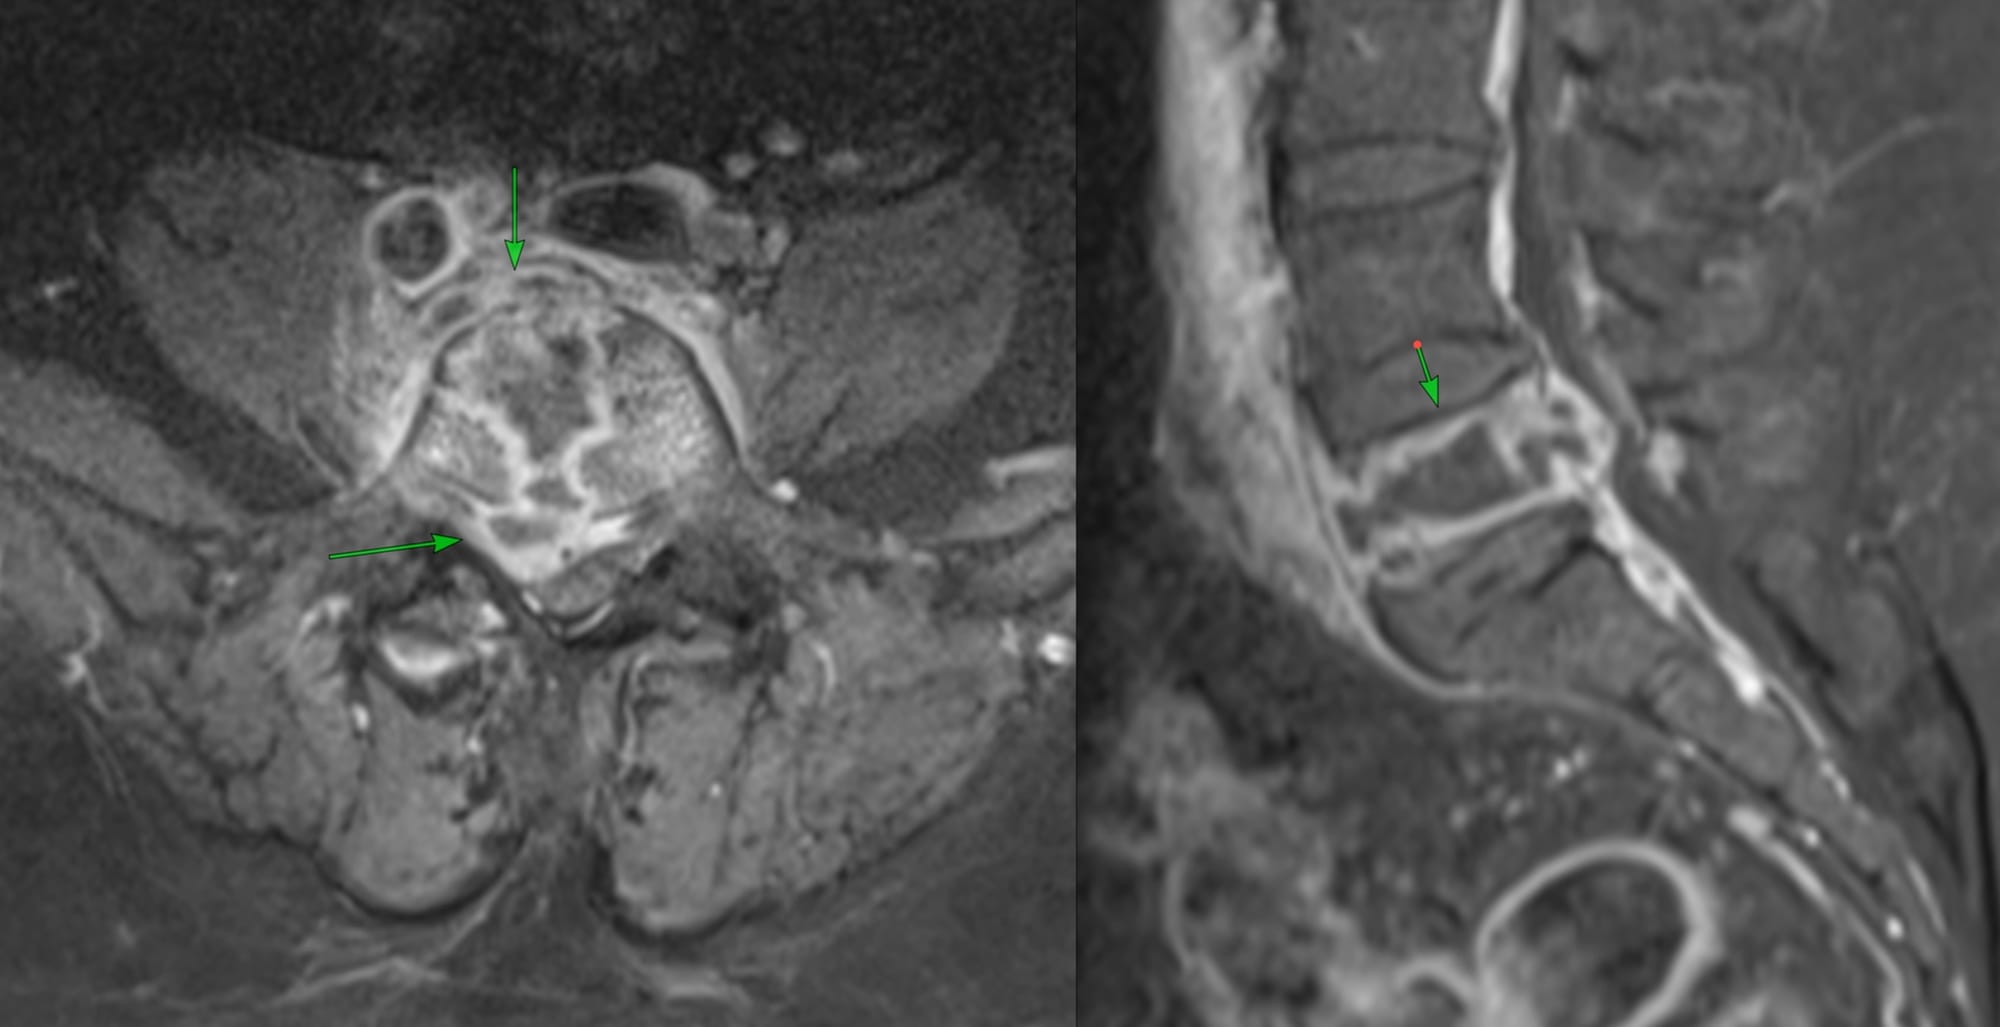

A 64-yrs old patient presented with low backache and MRI showed an osteolytic lesion in the L5 vertebral body.

She was referred for a biopsy. On the MRI, it seemed a transpedicular approach may be possible, but once she was prone, the only approach was through the facet joint.